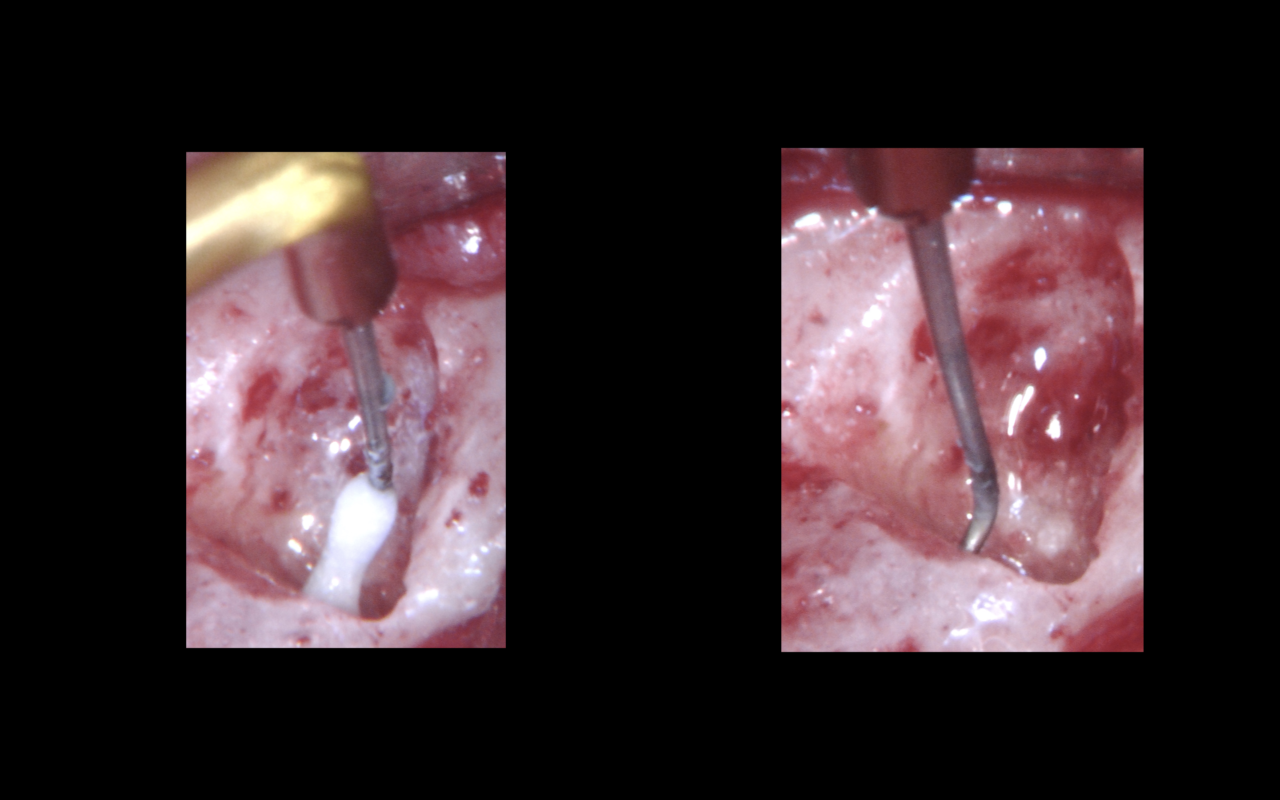

Attraverso la CBCT (Figura 2a) è possibile calcolare con precisione la posizione dell’apice radicolare. La breccia ossea e il taglio dell’apice radicolare (Figura 2b) sono eseguiti in modo conservativo. Dopo l’apicectomia, ad alto ingrandimento 24x e utilizzando un micro-specchietto è possibile notare l’area bianca centrale completamente calcificata (Figura 2c).

Nell’area calcificata si esegue la retro-preparazione utilizzando una punta ultrasonica (P-14D, Satelec) (Figura 3a). Dopo la retro-preparazione, grazie all’aiuto del microscopio operatorio, ad alti ingrandimenti (Figure 3b-c) si notano detriti all’interno dell’area preparata.